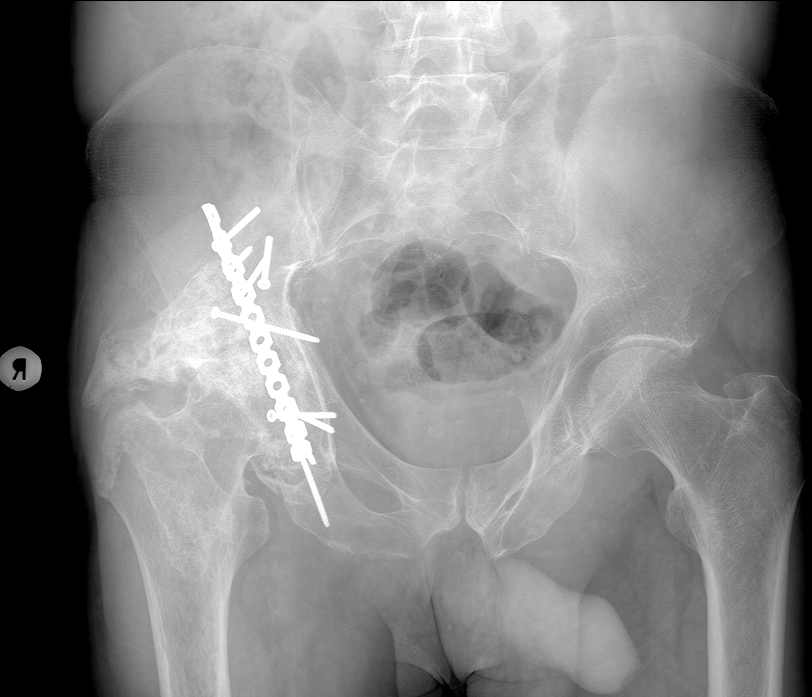

Сегодня посмотрим на эндопротезы суставов. Для начала коленных. На снимке видно, что они разные по конструкции, т.к. ставились с промежутков почти в 10 лет - в 2014 и в 2023 году: